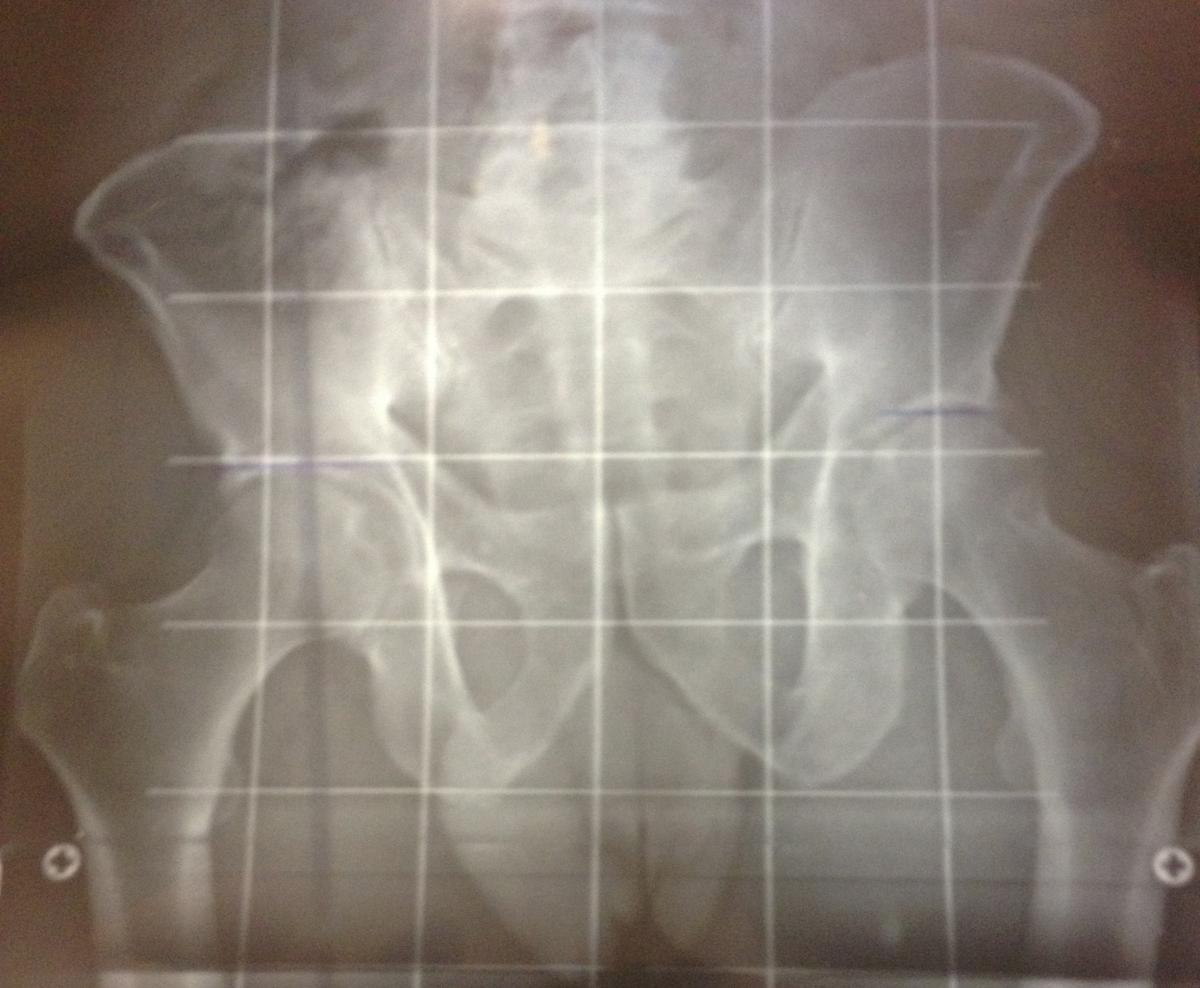

Telemetría, donde se puede apreciar la diferencia ósea de las extremidades inferiores del paciente

Ejemplo de caso clínico de dismetría de cadera

Esto es lo que le ocurrió a uno de nuestros pacientes que acudió a la consulta de Podoactiva aquejado por una fascitis plantar en un pie.

Desde Podoactiva, al realizar la exploración y revisión, se detectó una dismetría bastante acentuada que hasta entonces ningún especialista había percibido en el paciente. Las dismetrías son complejas de diagnosticar y existen diversas técnicas. Para ello, se utilizan procedimientos incluidos dentro del estudio biomecánico de la pisada, por ejemplo, el uso de plataforma de presiones tiene una gran precisión de diagnóstico y aportan un amplio abanico de parámetros.